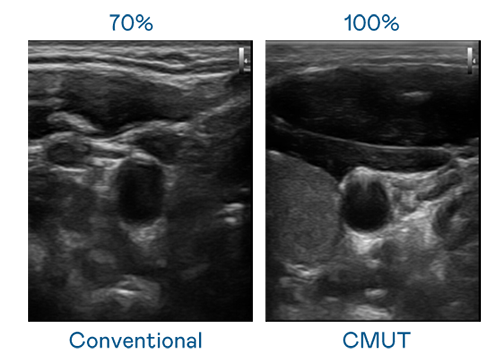

CMUT 技術是一種用電容式微機電元件來產生超音波訊號的技術。與傳統 PZT 壓電式技術相比,CMUT 頻寬增加 30%,更寬頻的超音波訊號讓影像解析度大幅提升,是實現高影像品質醫療超音波掃描、促進精準醫療發展的關鍵技術。

大頻寬帶來超清晰影像

超音波影像的解析度高低,首先取決於探頭能發出的訊號頻寬。ag真人国际官网 CMUT 可提供高清晰的超音波訊號,提供高頻寬、高靈敏度、影像紋理細節更高的超音波影像,協助醫護人員縮短影像判讀時間及利用精準的醫療影像進行診斷。